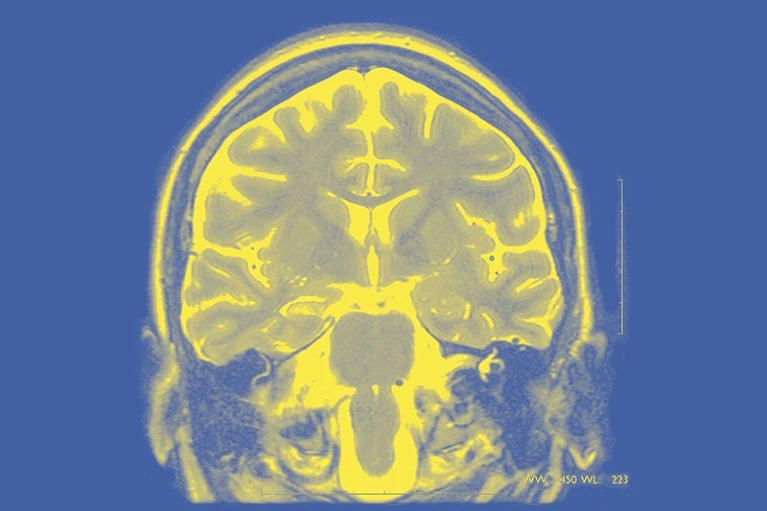

Виртуальная модель мозга поможет нейрохирургам лечить эпилепсию

Виртуальные модели мозга людей, страдающих эпилепсией, должны помочь более эффективному лечению этого заболевания. Они показывают нейрохирургам, какие именно зоны отвечают за припадки. В настоящее время этот подход тестируется в клиническом испытании под названием EPINOV. Тесты позволят оценить, повышает ли новый метод процент успешных операций по лечению эпилепсии.

Нейрохирургам, чтобы распознавать зоны мозга, ответственные за эпилептические припадки, приходится делать диагностическую трепанацию, и даже это не всегда помогает. Виртуальная модель мозга должна радикально усовершенствовать диагностику эпилепсии.

Виртуальные модели мозга людей, страдающих эпилепсией, должны помочь эффективному лечению этого заболевания, показывая нейрохирургам, какие именно зоны отвечают за припадки.

Модели, созданные с помощью вычислительной системы, известной как Виртуальный эпилептический пациент (VEP), были разработаны в рамках проекта "Мозг человека" (HBP), десятилетней европейской инициативы, направленной на цифровые исследования мозга. В настоящее время этот подход тестируется в клиническом испытании под названием EPINOV.